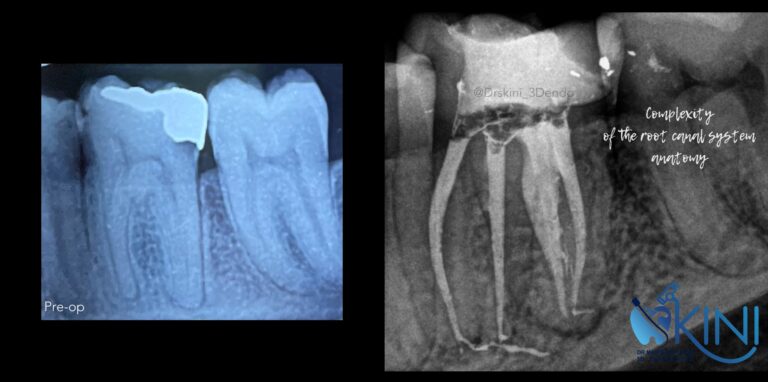

درمان ریشه تخصصی

◦ درمان ریشه برای دندان هایی با انحنا شدید ◦ دندان هایی با کانالهای بسته ◦ درمان مجدد دندانهای شکست خورده ◦ درمان ریشه دندانهای عقل قابل نگهداری ◦ درمان دندانهای نرمال

بنده افتخار این را داشتم که از شهر اصفهان جهت درمان ریشه خدمت این کادر درمان مجرب برسم و یک کار فنی و حرفه ای را شاهد بودم.

ای کاش خانم دکتر اسکینی را میشد هزاران کپی ازشون گرفت و در کل این سرزمین جای داد. بنده اولین بار بود که در سن 43 سالگی شاهد یک درمان ریشه بسیار عالی بودم و ای کاش افتخار میدادن و دندان بنده را پر میکردن ولی ایشون فرمودن هر کاری تخصص جدایی دارد.